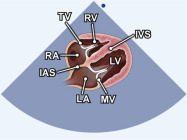

| 2.14. Mặt cắt 4 buồng từ mỏm |

||||||||

|

|

Cửa sổ siêu âm từ mỏm tim Mặt cắt 4 buồng

Bệnh nhân nằm nghiêng trái, xác định diện đập của mỏm tim, marker đầu dò hướng về giường bệnh |

Nhĩ trái (LA)

Van hai lá (MV) Thất trái (LV) Vách liên thất (IVS) Thất phải (RV) Van ba lá (TV) Nhĩ phải (RA) Vách liên nhĩ (IAS) |